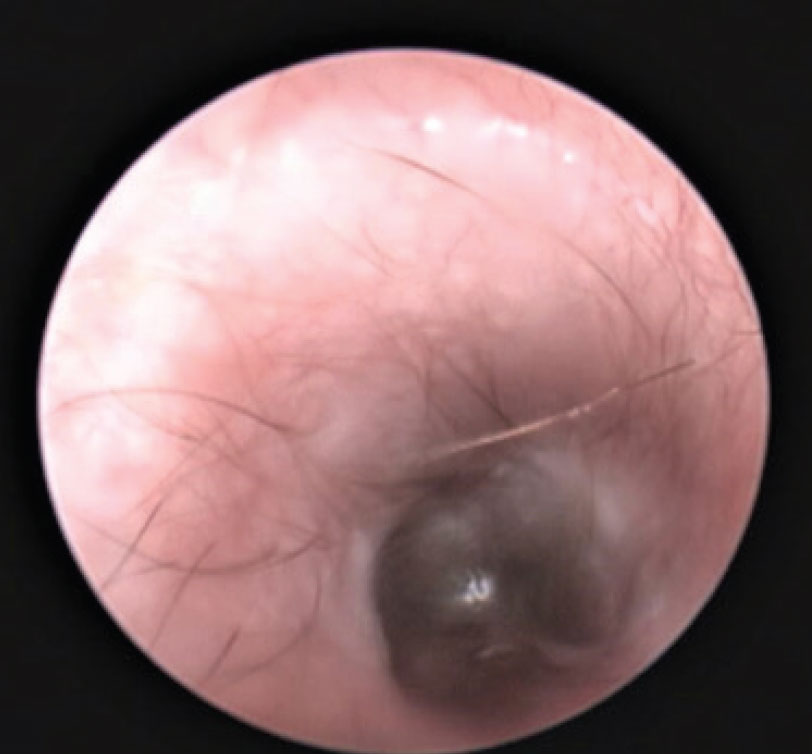

Reversing the changes associated with inflammation, ie. oedema, erythema and exudation, and treating secondary microbial infections will restore the epithelial migration. Glucocorticoids are indicated to reverse the oedema, erythema and exudation. Antimicrobials are indicated for the infection. Once treated the epithelium should be smooth, glistening and pale (Figure 3). The sooner the swelling is reversed, and drainage re-established, the less likely it is to lead to chronic irreversible changes.

Figure 3: Post treatment, the epithelial lining should be smooth and pale.